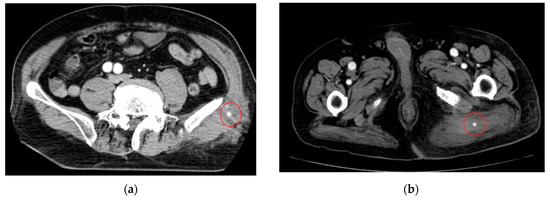

- AI for Image Analysis: AI-based image analysis algorithms can enhance the detection and diagnosis of extravasation events in imaging studies, such as ultrasound, MRI, and CT. These algorithms can automatically identify subtle signs of extravasation, assist healthcare providers in interpreting the imaging findings, and facilitate a timely intervention. This suggestion is subsequently extended as a separate discussion.